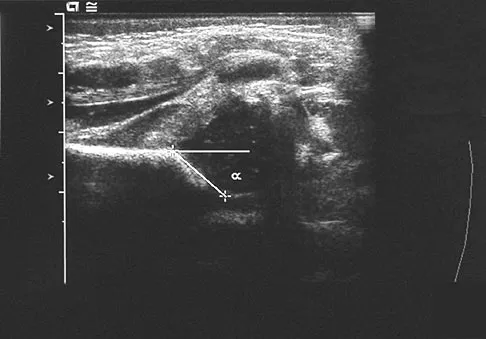

Question 100

A newborn girl with an isolated unilateral dislocatable hip is placed in a Pavlik harness with the hips flexed 100 degrees and at resting abduction. Figure 23 shows an ultrasound obtained 2 weeks later. What is the next step in management?

Explanation